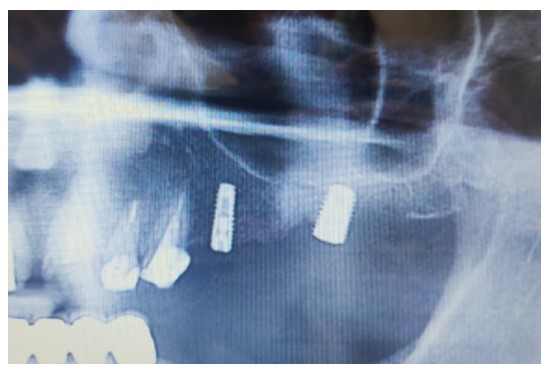

A female patient in her 50s sought rehabilitation for the posterior maxilla with a fixed implant-supported prosthesis. Clinical examination revealed missing maxillary premolars and molars, with residual roots in the maxillary first molar region. OPG and CBCT scans indicated sufficient bone for implant placement in the premolar region, and residual roots were noted in the molar region (Figs. 5 and 6).

Two MegaGen ST implants (MegaGen Implant Company, South Korea) were placed. At the four-month follow-up, the maxillary first molar implant was exposed, with a significant periodontal pocket detected around it despite stability. OPG revealed bone resorption around the implant (Fig. 7), and CBCT identified a 0.5 mm radiopaque mass resembling residual roots. The implant was removed, the mass was excised, and the area was cleaned. Histological analysis confirmed osteosclerosis (Fig. 8).

Preoperative scan showing the location of the lesion noted when reviewing scans after implant failure.

OPG 6 months after surgery showing significant bone resorption around the dental implant.